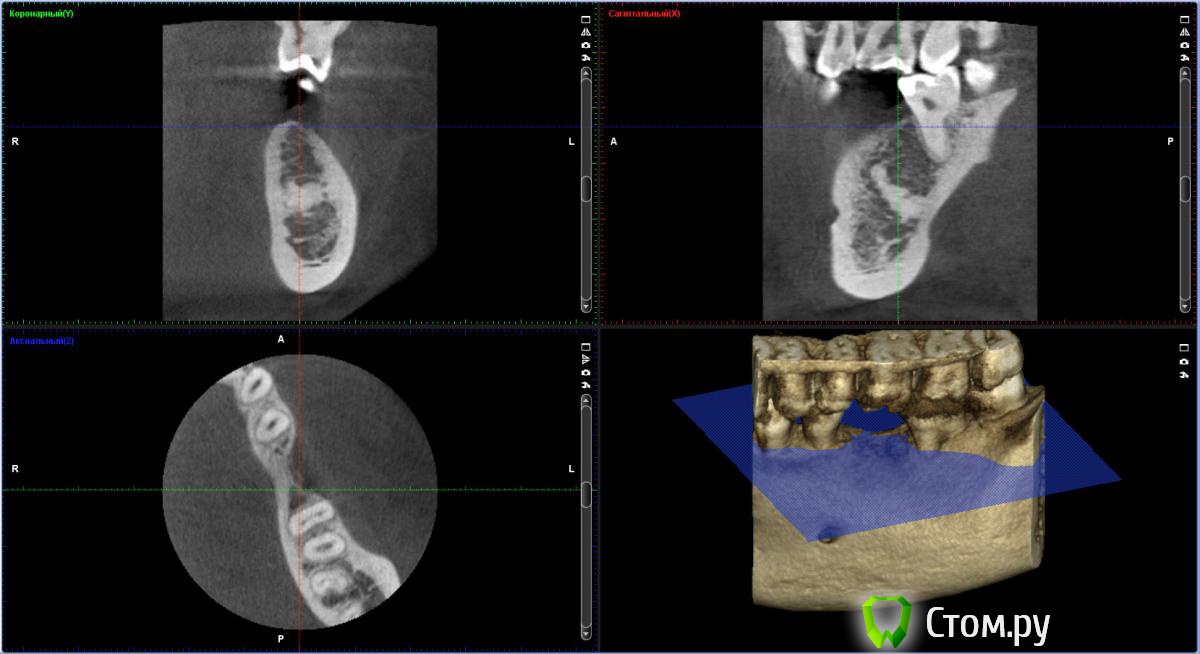

bobrdobr Опубликовано 17 февраля, 2014 Автор Поделиться Опубликовано 17 февраля, 2014 Добрый всем день. Сделал КТ. Снимок выложил на Яндекс.Дискhttp://yadi.sk/d/-CHDNu-nJ45Wy Посмотрите пожалуйста. Вопрос прежний: нужна ли костная пластика в каком-то виде перед установкой винтового импланта? Ссылка на комментарий

IvanK Опубликовано 17 февраля, 2014 Поделиться Опубликовано 17 февраля, 2014 Выложите скриншоты, не все могут/хотят качать Ссылка на комментарий

bobrdobr Опубликовано 17 февраля, 2014 Автор Поделиться Опубликовано 17 февраля, 2014 Хорошо. Так подойдет? Ссылка на комментарий

IvanK Опубликовано 17 февраля, 2014 Поделиться Опубликовано 17 февраля, 2014 нет) Ссылка на комментарий

Bier Опубликовано 17 февраля, 2014 Поделиться Опубликовано 17 февраля, 2014 судя по фото, скорее всего нужна. От КТ нужен срез горизонтальной плоскости - вид сверху на костный гребень, на 1 мм ниже его вершины. Ссылка на комментарий

bobrdobr Опубликовано 18 февраля, 2014 Автор Поделиться Опубликовано 18 февраля, 2014 (изменено) Имплант был предложен Semados 4,1*11,5 без костной пластики. судя по фото, скорее всего нужна. От КТ нужен срез горизонтальной плоскости - вид сверху на костный гребень, на 1 мм ниже его вершины. Сейчас попробую. Прикладываю 4 снимка: на уровне гребня (как мне кажется) и на 1,2,3 и мм. ниже. Изменено 18 февраля, 2014 пользователем bobrdobr Ссылка на комментарий